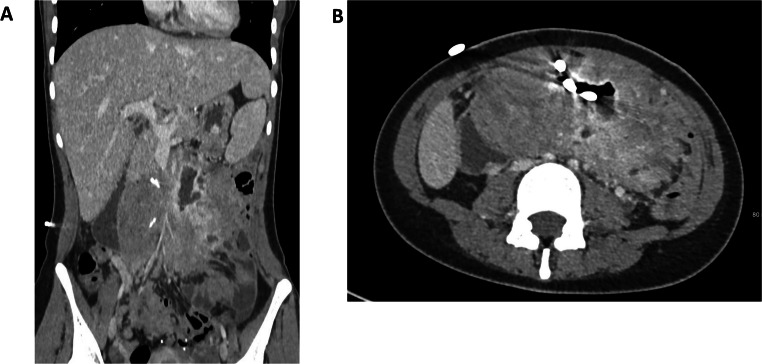

In patients with Familial Adenomatous Polyposis (FAP), large desmoid tumors can develop all over the body. However, the most frequent presentation is as large intra-abdominal masses, usually located in the mesentery of the small bowel. From there, they tend to grow and invade both the abdominal wall and/or the retroperitoneal structures. This can cause life-threatening complications such as recurrent abdominal sepsis with fistulation and damage to vital organs. In selected patients, the only option may be radical resection and replacement by intestinal transplantation (ITx). We aimed to review all the current literature on ITx for FAP-related desmoids and provide an update from the largest single-center experience (2007-2024). All patients undergoing ITx for FAP-related desmoid were included. Between 2007 and 2024, 166 ITx was performed in 158 patients at Addenbrooke's Hospital, Cambridge, UK. Of these, 20 (12%) were for desmoid associated with FAP (10 modified multivisceral transplants, 8 isolated ITx and 2 liver-containing grafts). The five-year all-cause patient survival was 92%, median follow-up was 4.3 years. As the patients presented with very advanced disease, many technical challenges were faced such as: extensive ureteric involvement, abdominal wall fistulation, management of previously formed ileo-anal pouches and extra-abdominal recurrences. Graft selection was another evolving issue, as foregut resection- versus sparing techniques require careful preoperative risk stratification due to increased long-term cancer risk in FAP patients. For certain patients with advanced FAP/desmoid disease, ITx can allow for a radical resection with excellent survival and functional outcomes. However, there is a high degree of initial morbidity associated with the operation and patients should be appropriately counselled. Graft selection and degree of native organ resection requires a careful balanced discussion.

Abstract Image